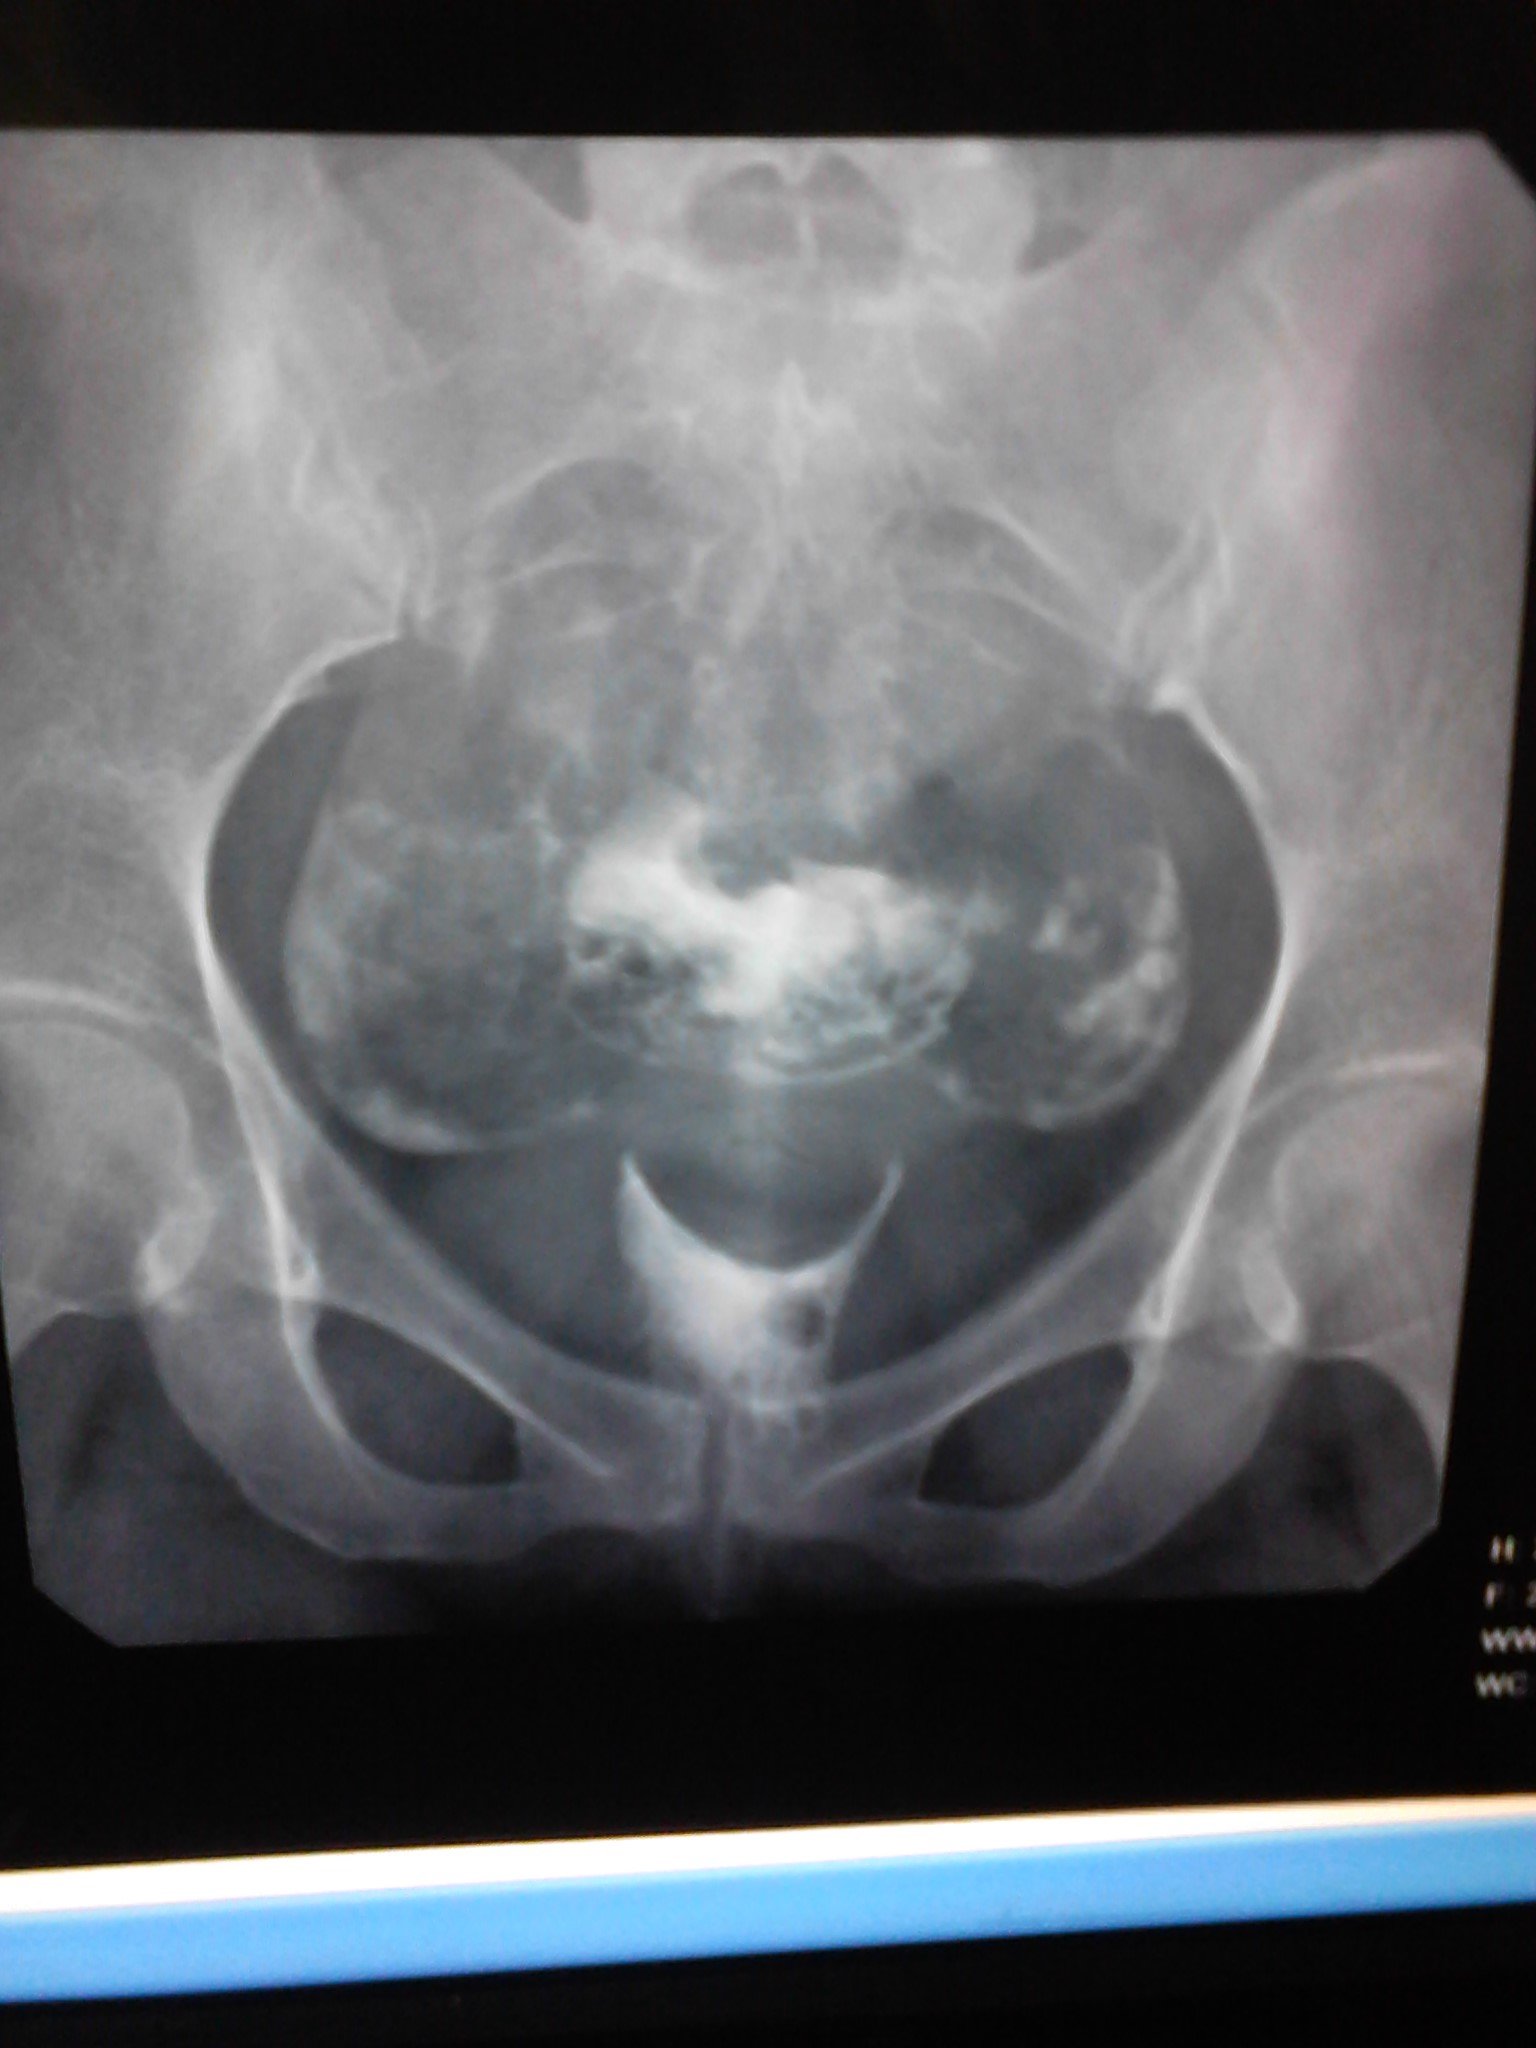

请大家看看造影的报告单,,,还有怀孕的机会吗? 患者信息:女 25岁 贵州 遵义 病情描述(发病时间、主要症状等):子宫腔大小.形态无明显异常.子宫粘膜面光滑整齐.宫腔内见气囊及气泡所致充盈缺损。双侧输卵管全程显影.双壶腹部粘膜皱襞增粗.双侧伞端呈锥状.其内造影剂呈喷射状进入腹腔.进入腹腔之造影剂弥散欠佳曾经治疗情况及是否有过敏、 遗传病 史:现在正在吃中药 点击展开 宇文令秋_1EAj 2012-06-17 13:32 满意回答 帮顶。。。。。。。。。。。。 欧阳弘新_SmTk 2012-06-17 13:51 宝宝知道提示您:回答为网友贡献,仅供参考。 相关问题 医生看看我的造影报告单 数字化X造影检查报告单还能生育吗? 做完造影这样的结果,次月跟第三个月会怀孕吗

患者信息:女 25岁 贵州 遵义 病情描述(发病时间、主要症状等):子宫腔大小.形态无明显异常.子宫粘膜面光滑整齐.宫腔内见气囊及气泡所致充盈缺损。双侧输卵管全程显影.双壶腹部粘膜皱襞增粗.双侧伞端呈锥状.其内造影剂呈喷射状进入腹腔.进入腹腔之造影剂弥散欠佳曾经治疗情况及是否有过敏、 遗传病 史:现在正在吃中药